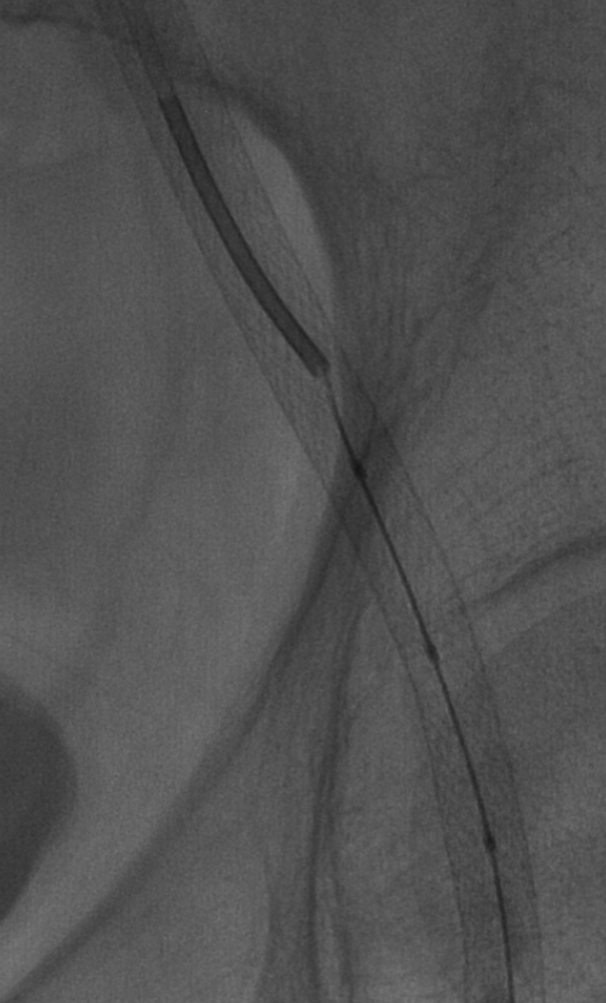

当地医院左侧髂动脉支架远端跨关节,至股浅动脉。

顺行穿刺无法开通,行左侧腘动脉逆行穿刺,超选进入顺行导管。